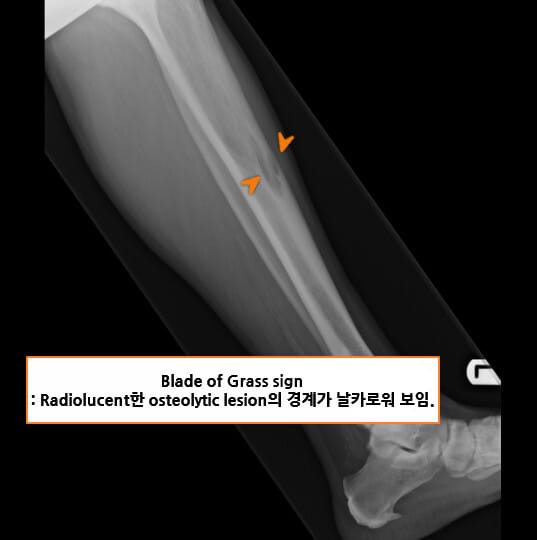

🟦 Blade of grass sign

장골의 골간(diaphysis)에서 관찰되며, 한쪽 방향으로 퍼지는 투과성 병변이 풀잎처럼 날카롭게 보입니다. 질병의 활동적 초기 병기 소견입니다.

• Blade of grass: 초기 골파괴 소견 (Osteolytic phase)